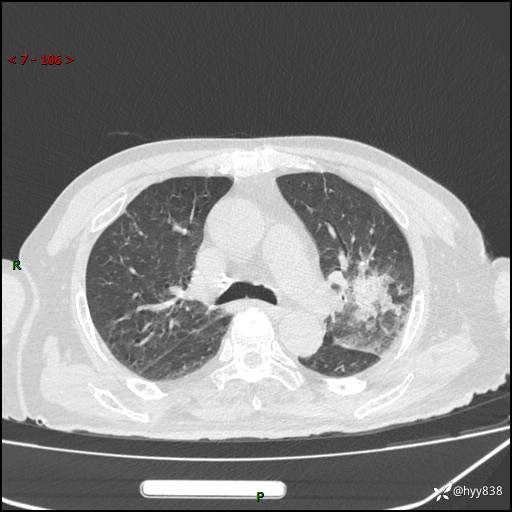

胸部CT平扫(2024.7.24)